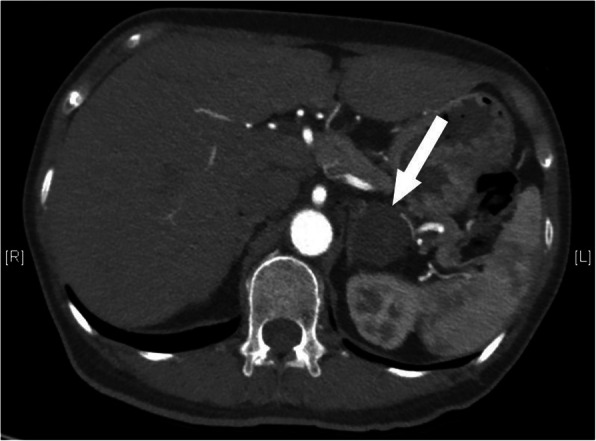

A 56-year-old woman presented to our hospital with a history of a left adrenal mass and high blood pressure. She had been diagnosed with hypertension in 2003. Her blood pressure was controlled with amlodipine and was less than 140/90 mmHg at a dose of 5 mg daily. She reported frequent fatigue. She was admitted to the hospital, diagnosed with hypokalemia and treated with potassium supplements. In 2009, she presented with chest pain and back pain. A computed tomography (CT) angiogram demonstrated dissection of the descending aorta (Fig. 1a). Thoracic endovascular aortic repair (TEVAR) with a stent graft was successful. At the same time, she was found to have a left adrenal mass approximately 1 cm in diameter. She was started on valsartan to reduce blood pressure. Her blood pressure was 130–140/90–100 mmHg initially but gradually became difficult to control. Despite treatment with three antihypertensive drugs, her blood pressure still reached 180/110 mmHg. In 2017, repeat aortic CT revealed no new dissection (Fig. 1b, c). CT of the abdomen showed that the left adrenal mass had grown to more than 3 cm in diameter (Fig. 2).

Fig. 2.

Abdominal CT. Left adrenal mass in 2017 (arrows). CT: computed tomography